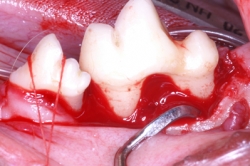

Los problemas que aquejan los tejidos periodontales son varios aunque su etiología primaria siempre es la misma, el alimento y las bacterias que se pegan a los dientes formando la placa dento bacteriana (PDB) y el sarro que destruyen lentamente pero de manera progresiva los tejidos de sostén dental. La enfermedad periodontal es la enfermedad de mayor incidencia y prevalencia en perros y gatos por lo que su diagnóstico, prevención y tratamiento es uno de los retos que el médico veterinario tiene en su trabajo clínico. La enfermedad periodontal es la causa más común de enfermedades como endocarditis bacteriana y artritis infecciosa por lo que el propietario y médico tratante deben de tener especial interés en la prevención y tratamiento de esta patología. La enfermedad periodontal se clasifica dependiendo de los tejidos afectados así como según el grado de destrucción del tejido óseo. Según el tejido afectado como “Gingivitis” cuando afecta la encía libre y papilar, y “Periodontitis” cuando ya afecta el tejido óseo y el ligamento periodontal formando destrucciones del hueso alveolar muy características de la enfermedad denominadas bolsas periodontales las cuales según la forma de destrucción pueden clasificarse como horizontales o verticales. La periodontitis se diagnóstica con una sonda periodontal que es un instrumento que tiene líneas de medición en su punta de trabajo y que se introduce en el surco gingival para medir en milímetros la destrucción ósea alveolar. Otro método de diagnóstico es la radiografía periapical en la cual se puede observar claramente el grado y forma de destrucción ósea alveolar.